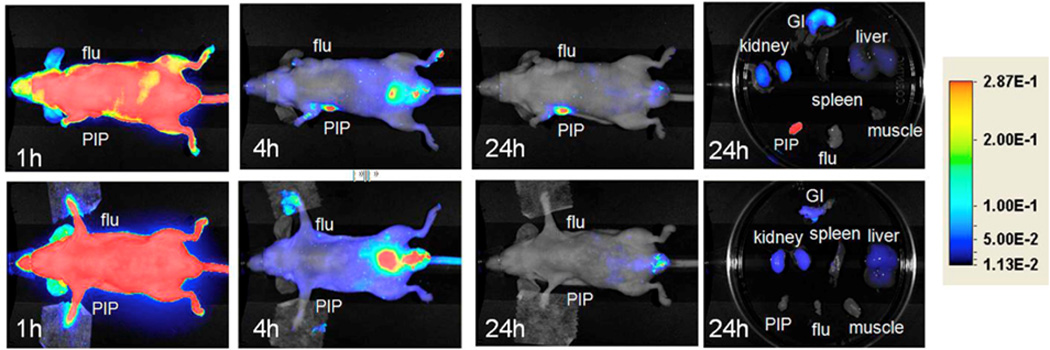

Multiple optical imaging agents targeting PSMA have been developed, some utilizing the J591 antibody with various light emitters, including radiotracers for Cerenkov emission [3; 36]. A few small molecule-based fluorescent agents have been developed as well, based on either phosphoramidate or urea-based peptidomimetics [17; 37]. While these agents currently remain in the pre-clinical realm (Figure 7), considerable efforts are underway to move them forward into clinical applications. A number of methods exist to perform whole-body tomography with fluorescent agents on animals [38], but at present there are no methods for applying this concept to whole body human scanning. Therefore, surface-based optical imaging (mostly intraoperative and endoscopic) is being pursued [39]. Enhanced intraoperative detection of cancerous lesions has been achieved with fluorescence-guided imaging and resection, using fluorescent dyes that target tumors [39–41]. Because of superior tissue penetration and decreased autofluorescence, dyes with emission in the near-infrared (NIR) window of the spectrum (650−900 nm) are preferred.

Figure 7.

Optical imaging. Top row: Images after administration of 1 nmol Cy7-3 at (left to right) 1, 4, and 24 h postinjection, as well as images of the excised organs at 24 h postinjection. Bottom row: Image after administration of 1 nmol Cy7-3 + 1 mmol DCIBzL, a high-affinity ligand for PSMA (blocker) at same time points as above. Note lack of uptake in the mice treated with DCIBzL, indicating binding specificity. With permission from Chen Y et al. (2012) Bioconjug Chem 23(12):2377-85